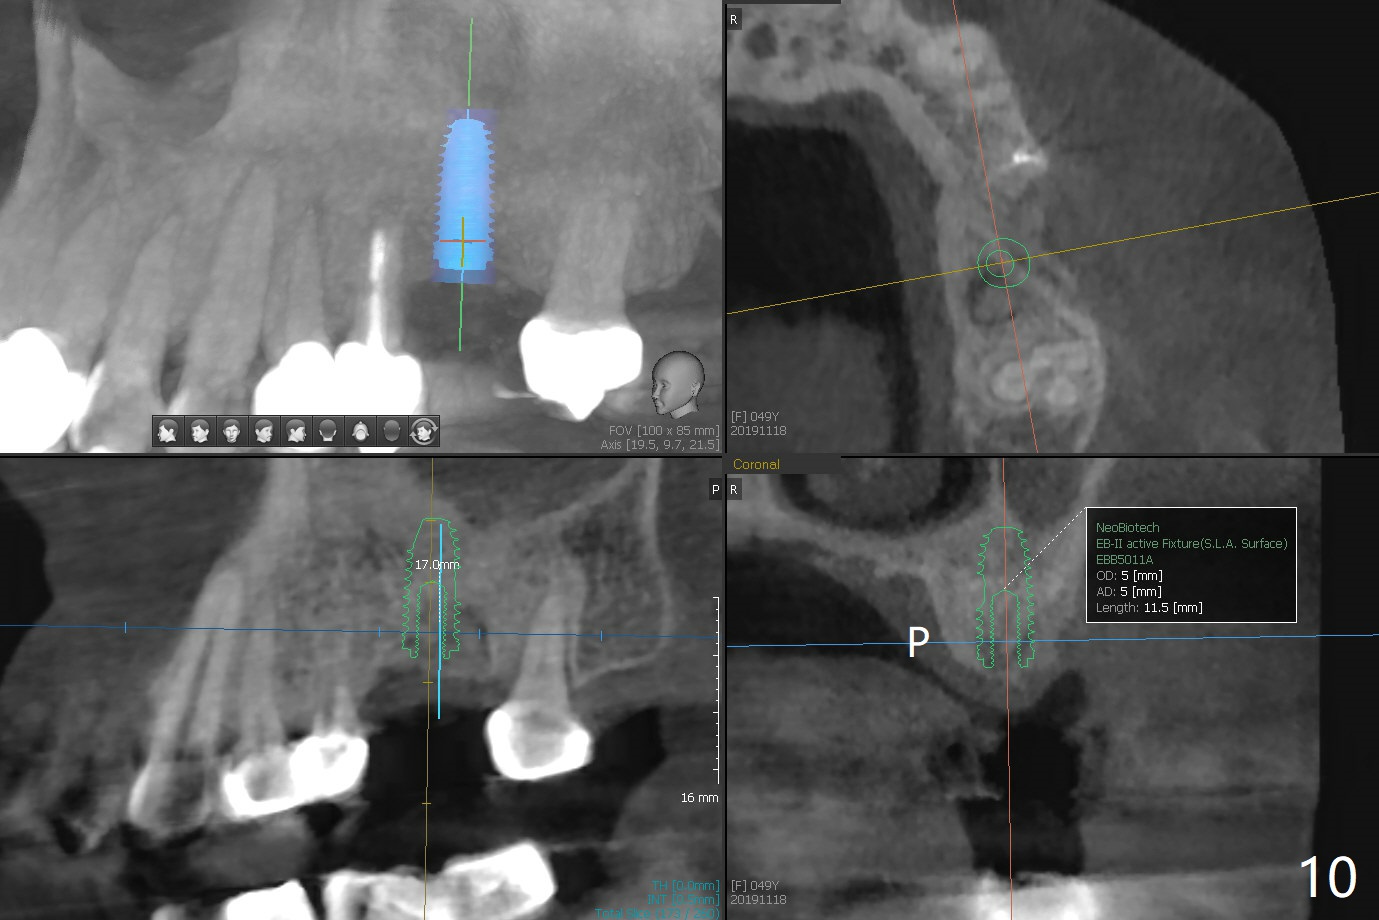

A 49-year-old woman returns for removal of the tooth #14 with loss of the buccal plate (Fig.1 red dashed line). After extraction, the buccal gingiva collapses as a dimple (Fig.2 ^). Cytoplast, a Titanium-Reinforced Non-resorbable Membrane (Fig.3), is used after bending (Fig.4) to assist in repair of the buccal plate with bone graft (Fig.5,6). As compared to Fig.1, the bone height also increases. Periodontal dressing and Cytoplast dislodge with odor 10 days postop (Fig.7,8). Periodontal dressing is re-applied. Spacer or acrylic dressing should have been used for security. In spite of the narrow ridge 5 months postop (Fig.9), a 5x11.5 mm bone level or 5x17 mm tissue-level implant is possible (Fig.10). But the implant should be placed more palatal, away from the buccal defect!